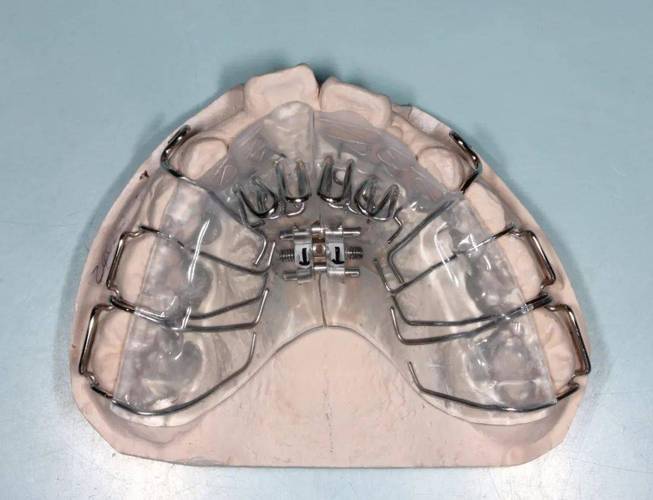

第三阶段:保持阶段

矫正结束后需佩戴保持器防止复发,常用哈雷保持器(附有钢丝和塑料基托)或透明压膜保持器,前3-6个月需全天佩戴,之后过渡至夜间佩戴,通常需保持1-2年,部分重度扭转患者需延长至3年。